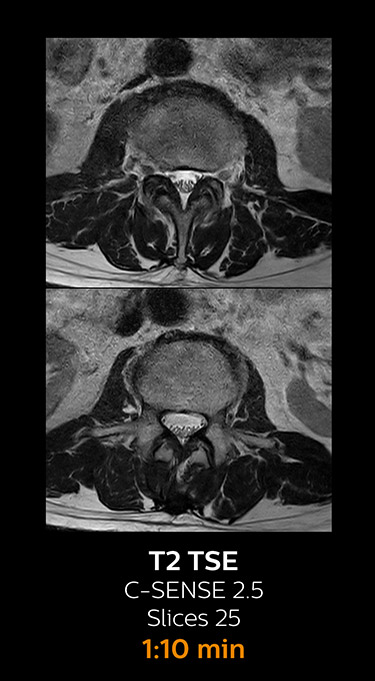

With Compressed SENSE, the scan time for the routine cervical spine examination at KNC was reduced from 13:11 to 9:52 minutes, which corresponds to 25% reduction.

MRI examination of the cervical spine with Compressed SENSE

Ingenia 3.0T CX

Scan time 9:52 min. (was 13:11 min. without Compressed SENSE)